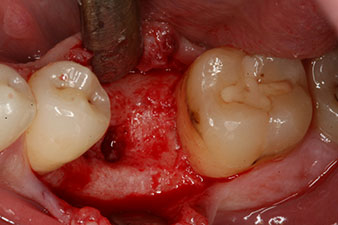

These values could have indicated open healing or even immediate restoration. Due to the insufficient crestal bone volume at the implant, the region was augmented with the bone chips collected during preparation of the implant bed and sutured to exclude saliva.

The implant was uncovered two months later and a gingiva former was screwed in (no picture).